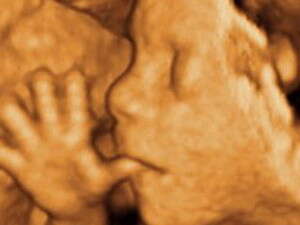

רופאים אמריקנים החלו להשתמש בבדיקה גנטית חדשה לנשים הרות, שמאפשרת לזהות מספר עצום של 150 הפרעות גנטיות. אך הבדיקה מעוררת מחלוקת ובעיקר חשש מפני בלבול וחרדה מיותרים אצל ההורים

הבדיקה החדשה הוצגה בפני הציבור בתקופה שבה נערך דיון אינטנסיבי סביב בדיקות הסקר לתסמונת דאון, המאפשרות לאבחן את התסמונת באמצעות דגימת מי שפיר או סיסי שליה. הבדיקה החדשה, שמכונה CGH Comparative genomic hybridization (הכלאה גנטית השוואתית), נסמכת על 'מערכי-מיקרו', או 'שבבי גנים', שמאפשרים את איתורם של עשרות תסמונות אשר אינן ניתנות לזיהוי באמצעות בדיקות הסקר הסטנדרטיות.